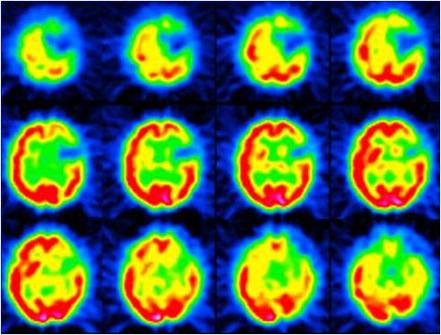

Recupero esta noticia sobre un tema tan interesante:

«El cerebro de los niños muy inteligentes se desarrolla según un patrón distinto del de aquellos que poseen capacidades más normales, según han descubierto unos investigadores tras analizar escáneres cerebrales recogidos durante 17 años. Algunos expertos esperan que el descubrimiento ayude a comprender la inteligencia en función de los genes que la favorecen y las experiencias infantiles que pueden fomentarla. «Es la primera vez que alguien demuestra que el cerebro crece de forma distinta en los niños extremadamente inteligentes»…

LEER MÁS EN:

http://elpais.com/diario/2006/04/04/salud/1144101603_850215.html